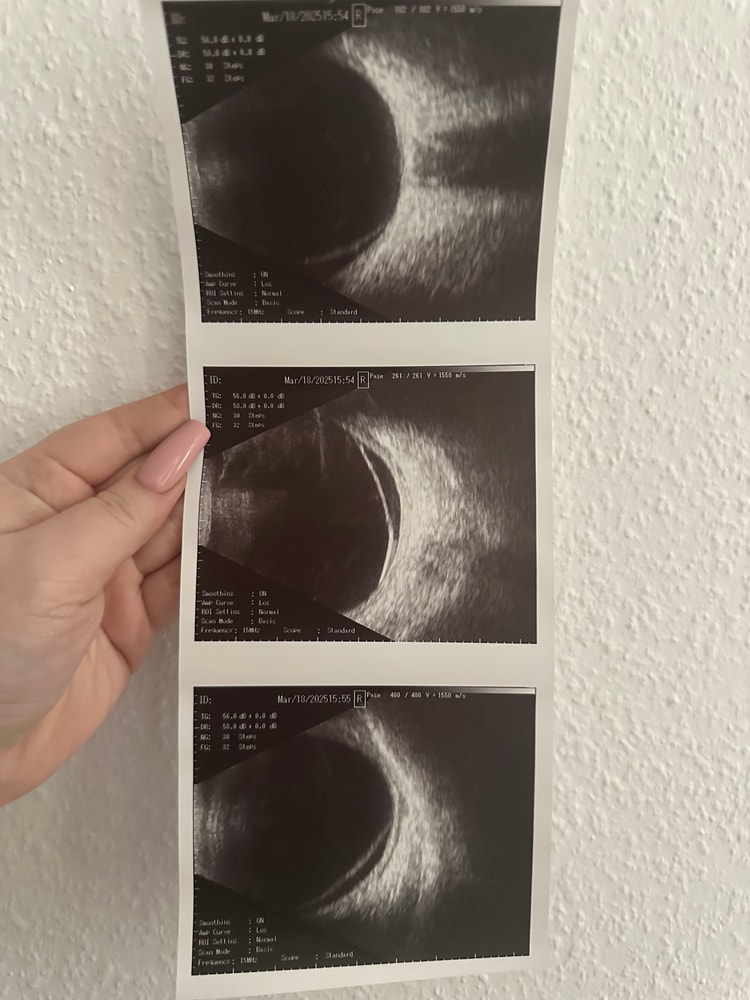

Анастасия Головина, спасибо за ответ. Прилагаю выписки. Посмотрите, пожалуйста, большая ли все таки отслойка? Один хирург сказал, что только пломбировать хирургическим путем. Заведующий клиники смотрел меня 2 раза и сказал, что коагуляции хватит, но исключить потужной период.

Ксения, да все верно, должны наблюдаться, по описанию по УЗИ с 5.30до 9 часов это не локальная, занимает два участка.

Анастасия Головина, то есть более одного квадранта, верно? И получается, что отслойка большая? Если так, то в таком случае это прямое показание к КС?